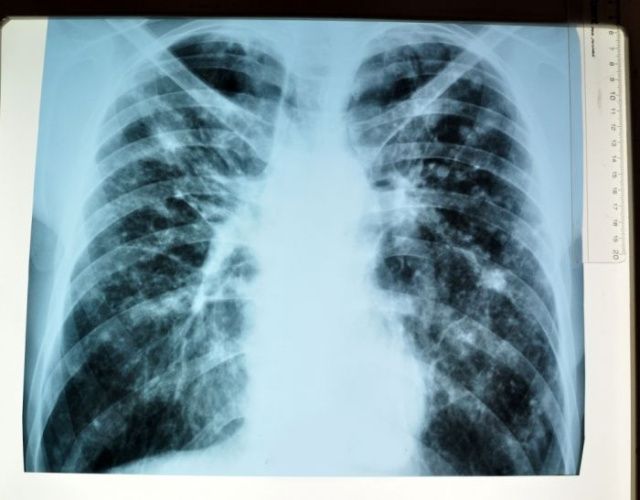

После проведенного необходимого объема лабораторно-инструментальных обследований мужчине был установлен предварительный диагноз "туберкулез с бактериовыделением", впоследствии подтвердившийся 5 августа.

В городском округе Жатай за период с апреля по май месяц текущего года выявлено шесть случаев заболевания туберкулезом. У всех больных диагностирована запущенная форма заболевания, в том числе у пяти лиц - с бактериовыделением. В данное время все выявленные лица получают лечение в стационаре профильного лечебного учреждения, сообщается на сайте пресс-службы Министерства здравоохранения РС(Я).